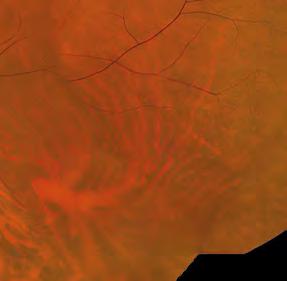

Dry eye patients at Park Vison have pre-treatment diagnostic measurements taken, including tear interferometry, tear film break-up time (TBUT), tear meniscus height (TMH), meibography, digital slit lamp images, fluorescein staining and a questionnaire on symptoms. This is not only important for clinical decision-making, but for patients to be able to see improvements.

Medmont Meridia TBUT and meibography